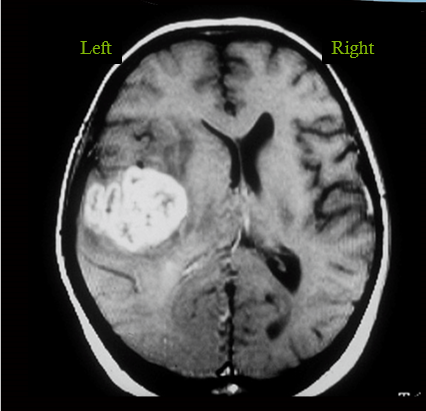

infarct in MCA territory leading to all loss of fibers losing vision on opposite side

occipital lobe lesion. alsmost superimposable field defects. left occipital lobe causing right sided visual field defect.

AVM malformation in left occipital lobe causing right sided visual field defect